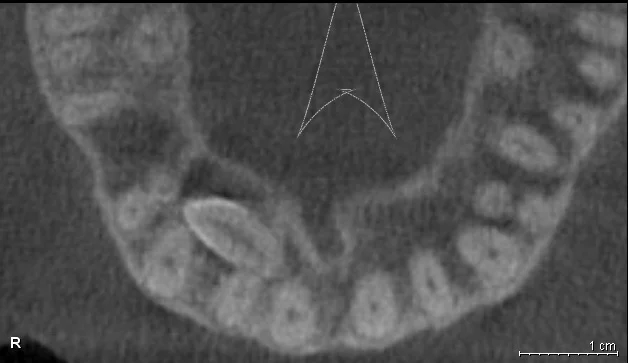

Давайте сравним снимки зубов, сделанные при помощи визиографа (слева), и при помощи компьютерной томографии (справа).

Как говорится, ощутите разницу. КТ - гораздо более точная и своевременная диагностика.

Воссоздавая орган (зуб) или даже совокупность органов, необходимо предельно точно знать исходную ситуацию. Корни зубов, каналы зубов, крупные сосудисто-нервные пучки, идущие внутри костной ткани, верхнечелюстная пазуха во всех подробностях и т.д. - в неискаженном виде все это можно увидеть только на компьютерной томограмме. Стоит ли говорить, что все эти структуры важны для имплантации, так как могут быть легко поврежденфы в ходе операции.